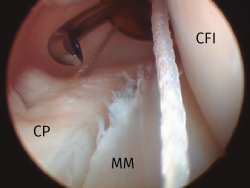

Durante este paso es importante identificar por transiluminación cutánea la vena safena interna (lo que se facilita reduciendo la intensidad de la luz ambiente en quirófano). De esta forma se establece también el trayecto del nervio safeno interno (que se localiza en posición posterior a la vena), realizándose el portal a una distancia aproximada de 1 cm por encima de dichas estructuras, evitando de esta forma dañarlas. Existe la posibilidad de variar discretamente la altura del punto de entrada en función de la intervención a practicar, situándose en una posición más proximal cuando se planea la reinserción con anclajes óseos de una rotura de la raíz posterior del menisco interno o, más distalmente, para la reparación de lesiones de la rampa meniscal mediante pasadores de suturas (Figura 3).

Figura 3. Reparación de una lesión de la rampa posterior del menisco interno, rodilla derecha. Uso de un portal posteromedial con una cánula de trabajo. Visión transescotadura. CFI: cóndilo femoral interno; CP: cápsula posterior; MM: muro meniscal.